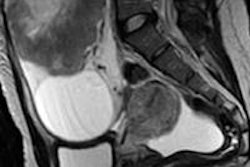

Gynecological neuroendocrine tumors don't get as much air time as DBT and breast cancer, but they are important nevertheless. They share certain characteristics radiologists need to know about, and it's also vital to differentiate these tumors from metastatic disease and other carcinomas. Find out more about these tumors.